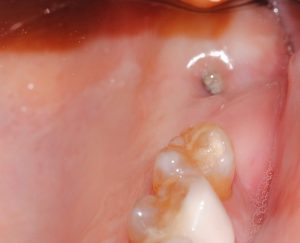

Estas son las imágenes obtenidas en la Exploración intraoral inicial:

- La paciente no soportaba las coronas antiguas sobre implantes, porque apoyaban sobre mucosa alveolar y no sobre encía queratinizada, invadiendo el espacio biológico.

- Mediante cirugía de acceso, se eliminó restos de biomaterial y tejido fibrosado que no estaban integrados y fistuilizaban la mucosa, presentando molestias e inflamación.